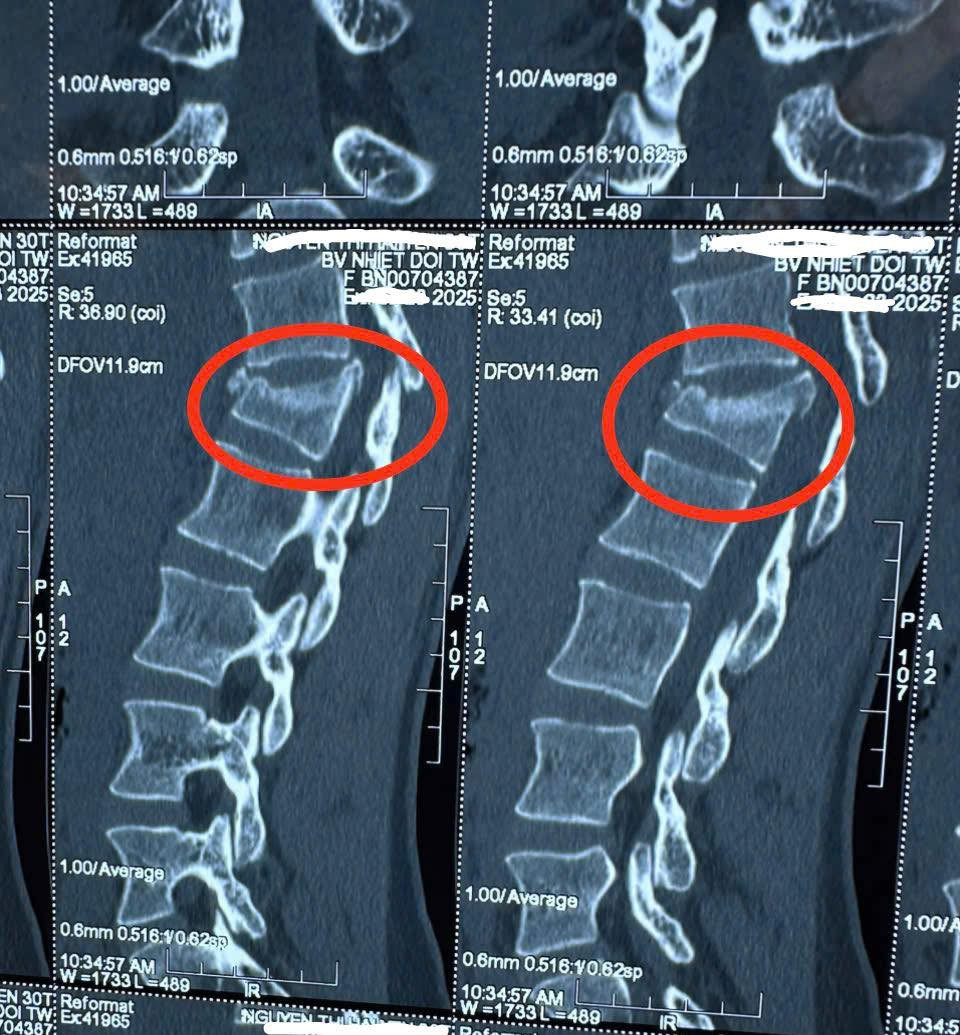

Tại khoa Cấp cứu, chị Y được khám lâm sàng phát hiện có vết thương hở dài 2 cm ở 1/3 giữa trước cẳng chân trái, đau cột sống lưng và mất vận động hoàn toàn. Kết quả X-quang và CT cho thấy chị Y bị xẹp thân đốt sống L1 và gãy gai sau đốt sống T12. Trước mức độ tổn thương nghiêm trọng, các bác sĩ khoa Ngoại chấn thương và Thần kinh cột sống đã hội chẩn và quyết định thực hiện phẫu thuật bằng phương pháp bắt vít qua da.

![]() |

| Hình ảnh cột sống của bệnh nhân. Ảnh: Bệnh viện cung cấp |